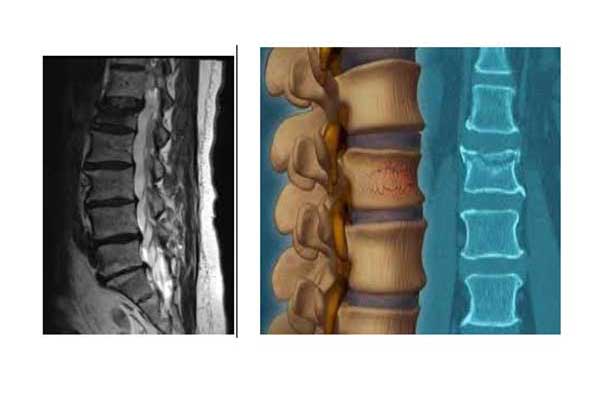

Transdermal kyphoplasty is a minimally invasive procedure for the treatment of vertebral compression fractures, which are fractures of the vertebral bodies that form the spine. When a vertebral body is fractured, the usual rectangular shape of the bone is compressed causing pain. These compression fractures can occur in one or more vertebrae in the spine and are usually a consequence of osteoporosis.

We use X-ray guidance to insert a balloon through a needle into the vertebral fracture, which extends upwards realigning the bone and creating a cavity within the vertebra. The fractured vertebrae are strengthened by the injection of special hardening material into the cavity when the balloon is removed. The surgical incision is about 0.5 cm.